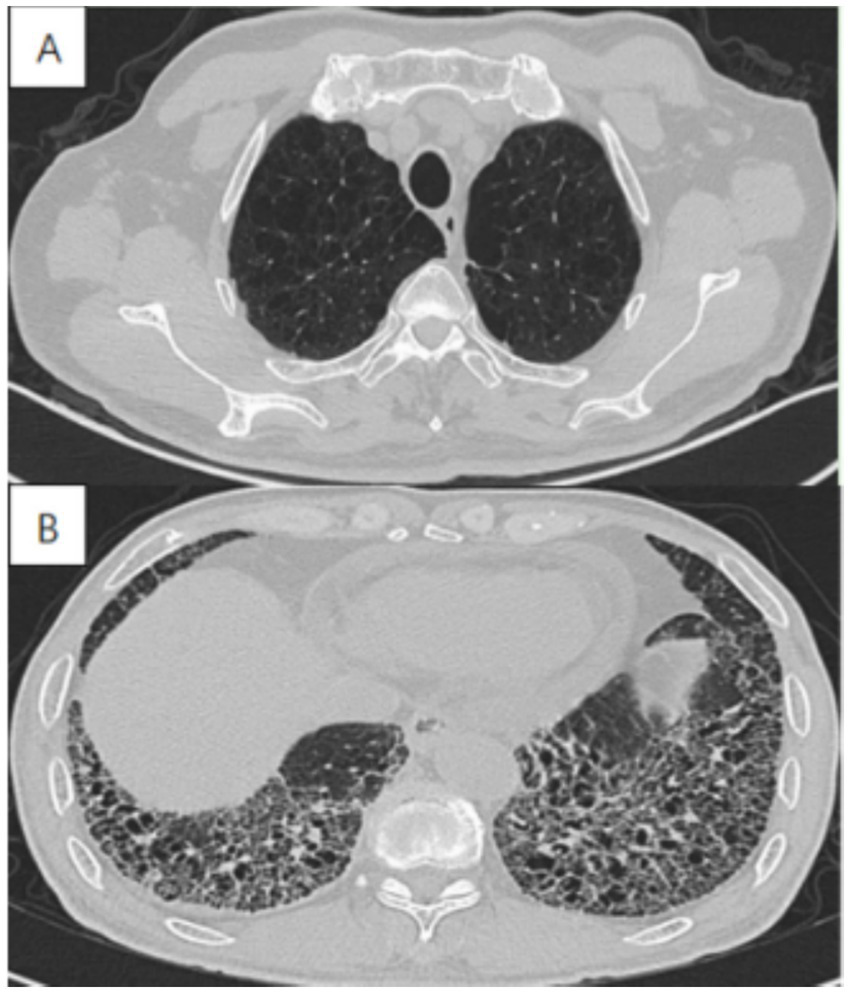

Imaging in CPFE reveals a characteristic dual pattern of upper-lobe emphysema and lower-lobe interstitial fibrosis (Figure 3). The emphysematous alterations in the upper lobes primarily consist of centrilobular and paraseptal bullae, exhibiting a distinct distribution pattern relative to pure COPD. Whereas centrilobular emphysema is predominant in COPD patients, paraseptal involvement is observed in approximately two-thirds of CPFE patientsāa signature feature of this syndrome (Table 1) (14, 32, 33). While emphysema and fibrosis are usually distinguishable on HRCT, their differentiation can be challenging during early disease stages or when both pathologies are diffusely distributed throughout the lungs. Hyperinflation leads to reduced pulmonary vascular markings and diaphragmatic flattening, which are hallmark radiographic features of advanced emphysema. Conversely, advancing fibrosis reduces the lung volume, reversing emphysema-associated overinflation. Mori et al. reported that, in comparison with patients with COPD alone, CPFE patients had considerably elevated KL-6 levels (20). These findings suggest that KL-6 has potential as a practical screening indicator for CPFE. Therefore, future studies should establish validated biomarkers for early CPFE detection and develop tools to discriminate fibrotic from emphysematous components.

Figure 3

High-resolution computed tomography in a 72-year-old male with CPFE, showing (A) paraseptal emphysema in the upper lobe, (B) lower-zone-predominant fibrosis.